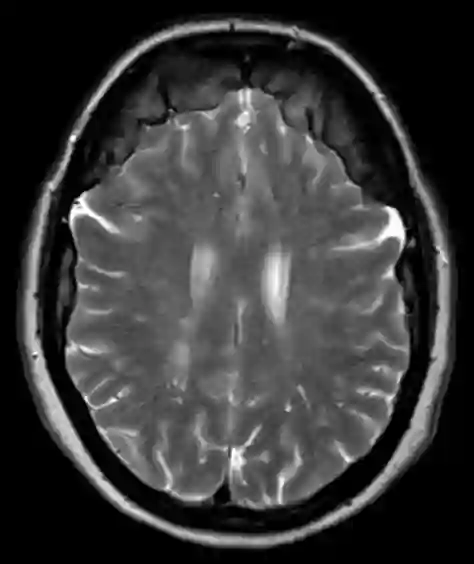

Bifrontale Hyperostose im MRT

Axiale T2 MRT Sequenz einer Patientin mit einer ausgeprägten bifrontalen Hyperostose.